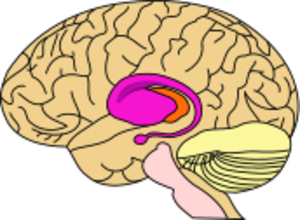

التغيرات الكبرى بسبب mHTT

Area of the brain damaged by Huntington's disease - striatum (shown in pink).